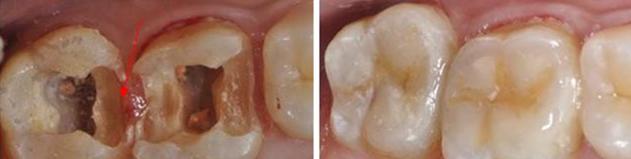

有啲蛀牙雖然外表睇上去只係一個小黑點,但其實內部已經齲壞嚴重,齲洞中嘅腐質含有大量被感染嘅牙體組織,補牙前需要去除齲洞中嘅腐質。如果唔將腐質去除乾淨就直接補牙,一方面充填材料好容易脫落,另一方面腐質中嘅細菌會繼續侵蝕健康嘅牙體組織,導致齲壞程度進一步加深。

補牙需要製備成一定形狀嘅窩洞來進行修復,醫生會在儘量唔破壞正常牙體組織嘅情況下,將腐質同埋剩餘較薄弱嘅牙體組織清除修整乾淨,從而獲得穩固嘅地基。

深圳補牙嘅流程大致分為口腔檢查、窩洞製備、窩洞消毒、窩洞充填等,其中磨牙就係窩洞製備時嘅操作。